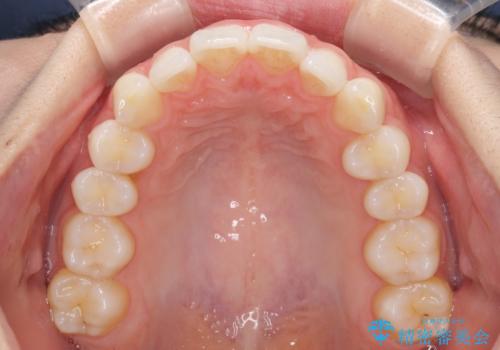

- 上下前歯の叢生を気にして来院された患者様です。

以前矯正をした後戻りということで、歯列不正はそれほど大きくなかったため、インビザライン・ライトを用いて矯正治療を行うこととしました。

前歯のデコボコが残っており、シミュレーション通りに動いていない部分がありましたが、再矯正であることやご本人の満足いくところまでデコボコが改善されたとのことで、治療を終了することとしました。